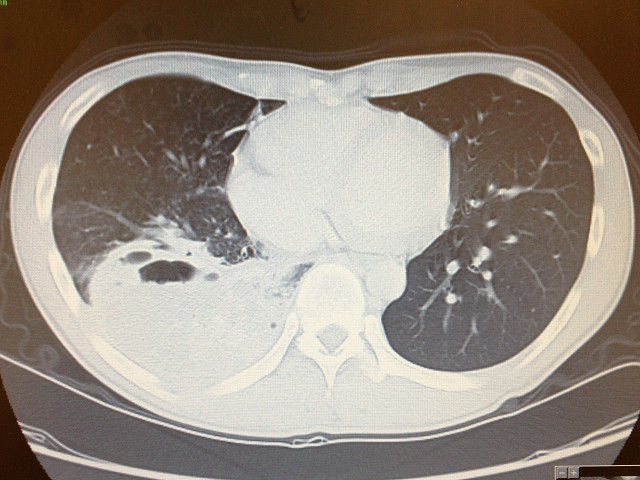

解答 解説 血痰を主訴に来院した70歳代男性 実践 画像診断q A 羊土社 レジデントノート 実践 画像診断q A 羊土社 レジデントノート 羊土社